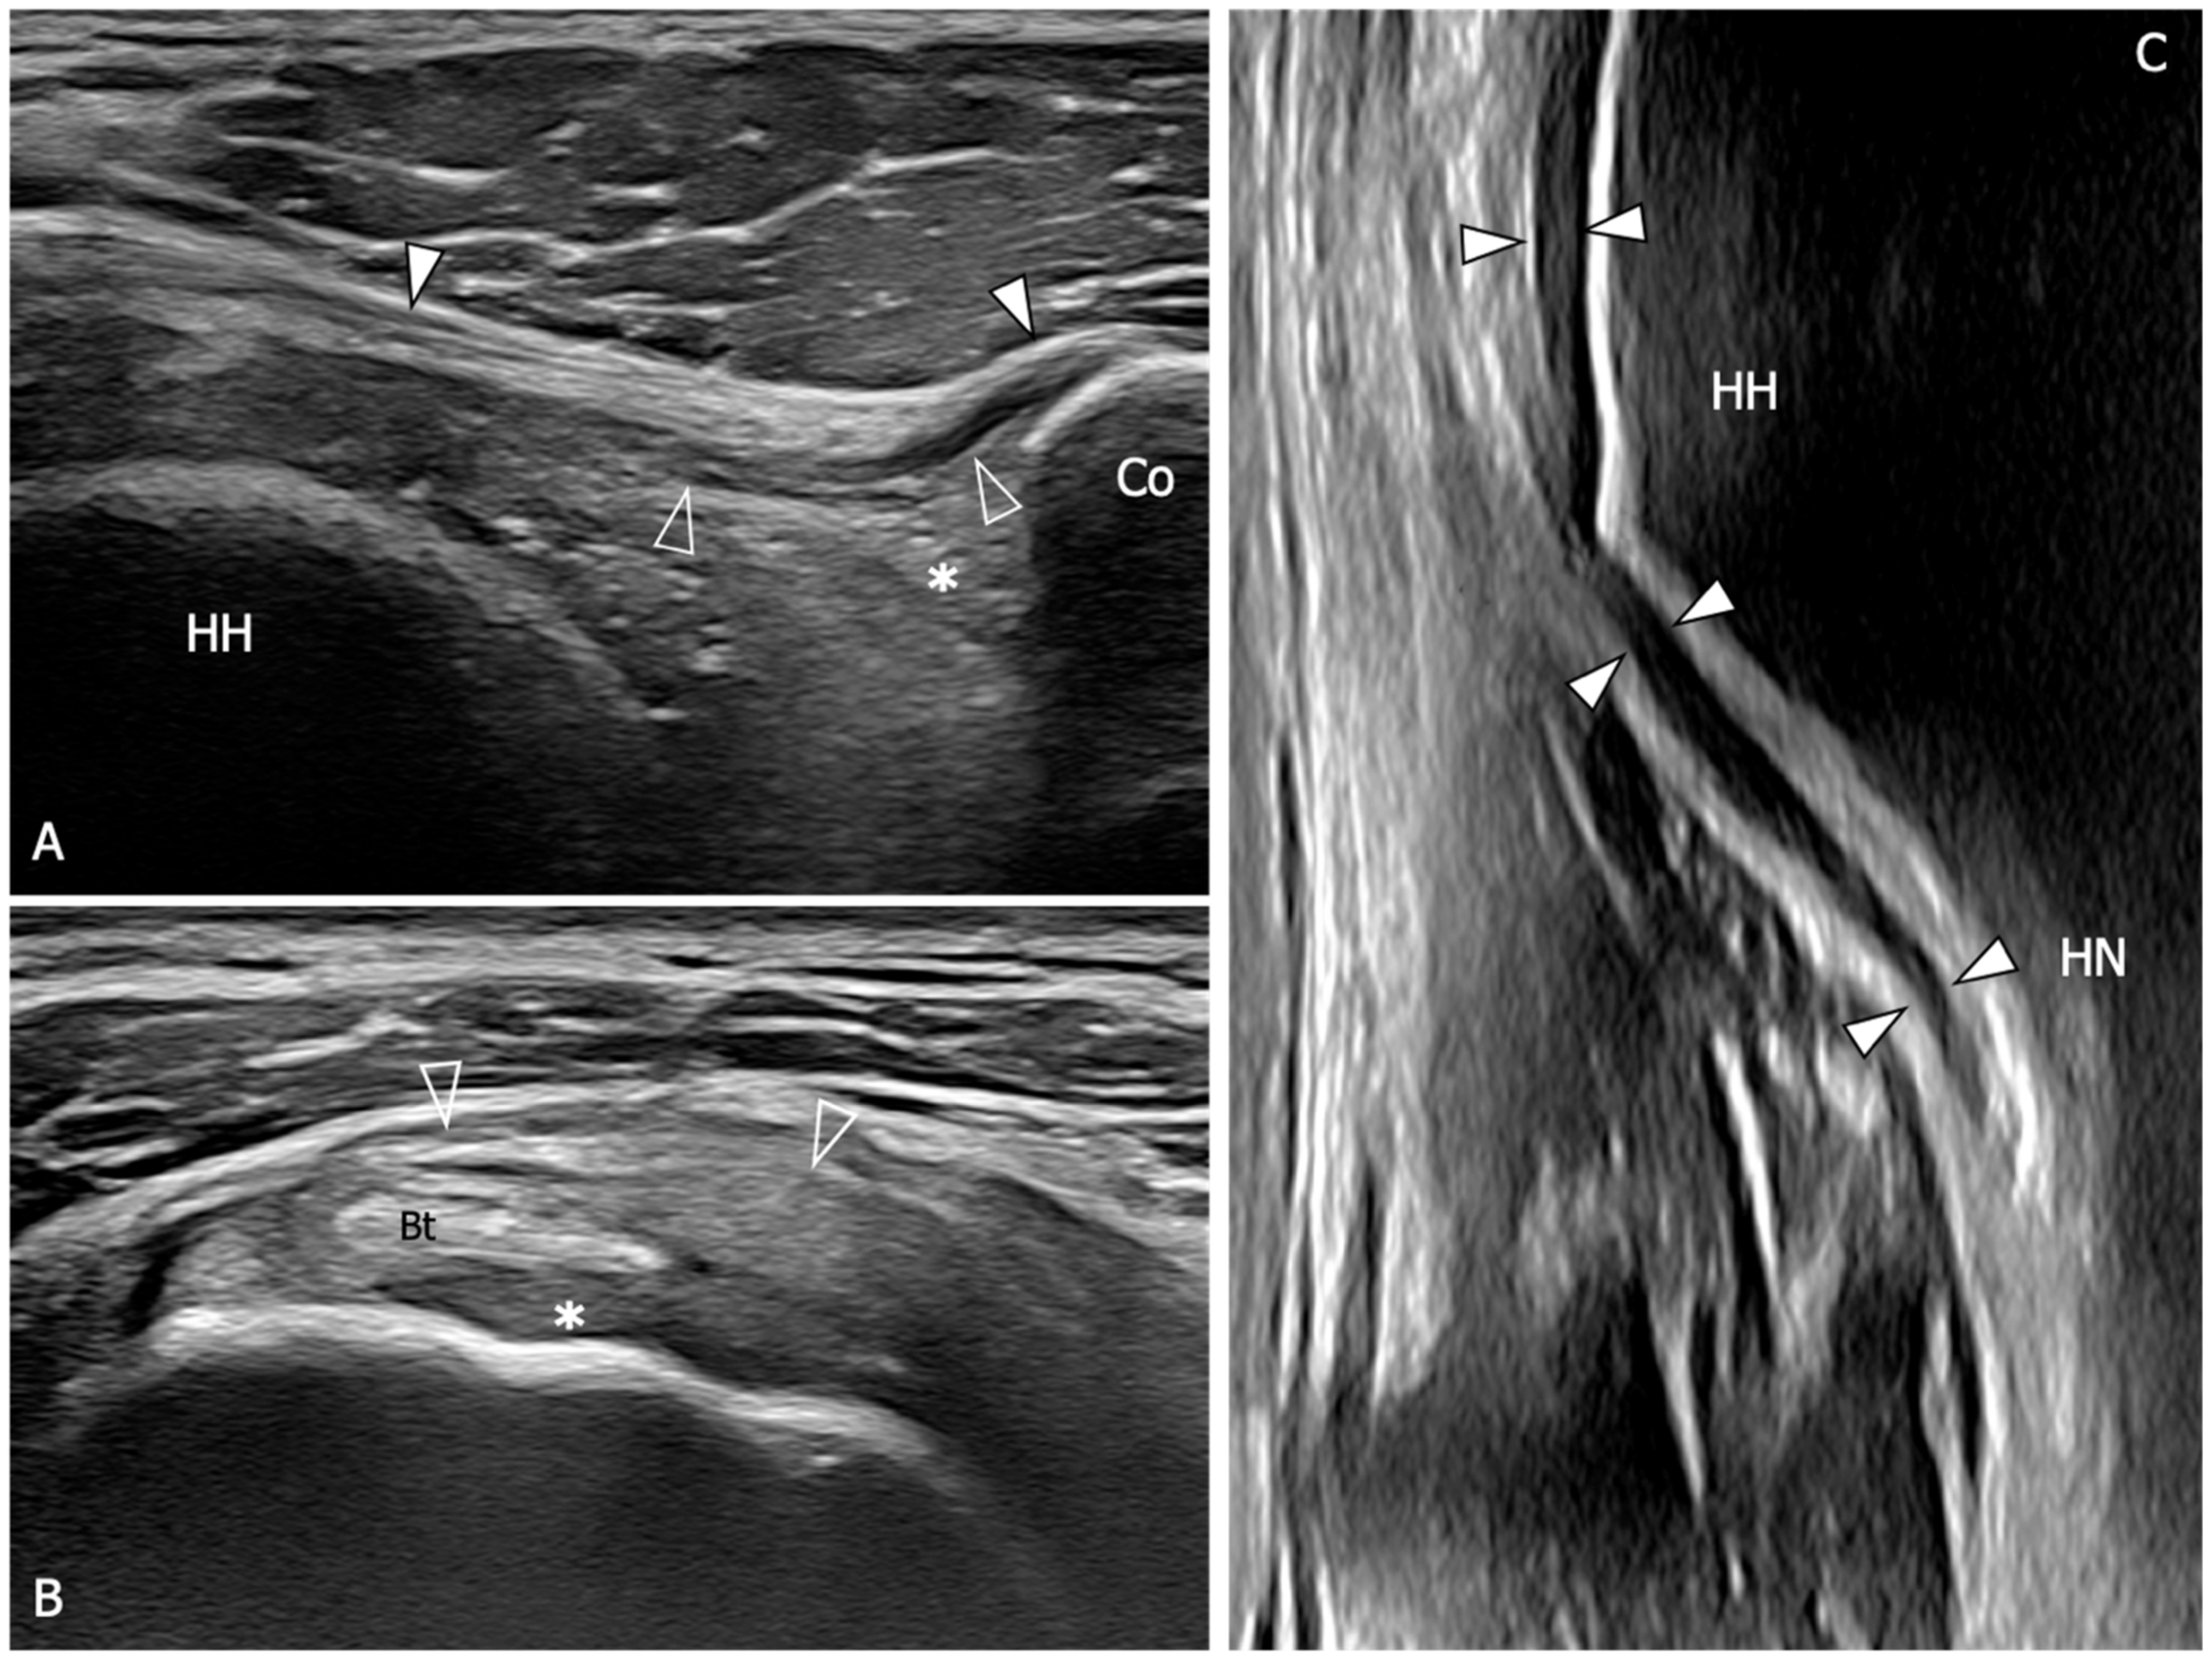

| An 88% sensitivity (95%CI: 74–95) and a 96% specificity (95%CI: 88–99) are demonstrated when US detect inferior capsule and coracohumeral thickening, rotator interval abnormality, and restricted range of motion. | [10] |

| The mean thickness of the axillary pouch capsule in patients with AC measured with US is 4 mm versus 1.3 mm in asymptomatic controls. | [61] |

| The axillary capsule thickness measured at its widest portion is 4.4 mm in the affected shoulder and 2.2 mm in the unaffected shoulder (p < 0.001). US measurements demonstrated good correlation with MR (p < 0.001, r = 0.83). | [62] |

| A cutoff value of 4 mm for axillary pouch thickness yielded a sensitivity of 93.8% and a specificity of 98% in diagnosing AC. A difference of 60% between the affected and the unaffected side may help in disclosing this condition also in patients with suggestive symptoms but axillary recess thickness less than 4 mm. | [63] |

| The average CHL thickness measure both in short and long axis was 3 mm in shoulders affected by AC. Painful shoulders without AC diagnosis exhibited an average coracohumeral ligament thickness of 1.39 mm; asymptomatic shoulders had an average coracohumeral ligament thickness of 1.34 mm. | [64] |

| Patients with AC exhibited a significantly thicker coracohumeral ligament (1.2 mm) compared to both subjects with painful shoulders (0.54 mm) and healthy volunteers (0.4 mm). | [65] |

| Patients with AC demonstrated a higher prevalence of effusion in the long head of biceps tendon sheath in the affected shoulder with respect to the contralateral side. | [66] |

| A greater amount of the long head of the biceps sheath effusion was found in patients with AC compared to patients with other causes of a painful shoulder. A negative correlation between the amount of effusion was found within the long head of the biceps tendon sheath and the glenohumeral range of motion. | [67] |

| Limitation in subacromial gliding of the supraspinatus tendon is found in 70.1% of patients with AC. The limitation of the supraspinatus tendon gliding beneath the acromion was demonstrated to be inversely correlated with the maximum amount of intra-articular injection for MRA. | [68] |

| US evidence of hypervascular soft tissue within the rotator interval demonstrated high sensitivity (97%) and specificity (100%) for the diagnosis of AC. | [69] |

| Microvascular analysis of the subcoracoid triangle demonstrated a sensitivity of 76.92% and a specificity of 91.43% in diagnosing AC. The cutoff for the area of vascular flow detected during the examination of the subcoracoid triangle was set at 1.31 mm2. | [70] |

| The injected volume of sonographic contrast did not differ significantly between healthy controls and patients with AC (19.0 ± 0.22 mL vs. 18.3 ± 0.29 mL, p = 0.07). However, the latter had a significantly smaller axillary recess volume compared to controls and showed more frequent filling defects in the joint cavity and synovitis-like abnormalities (91.1% vs. 13.3% and 75.6% vs. 22.2%, respectively). | [71] |